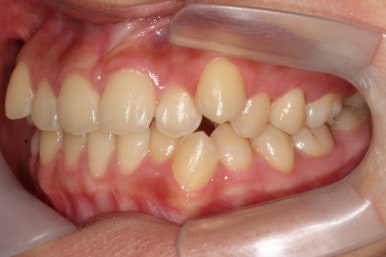

부산교정전문의 키다리아저씨치과에 처음 내원하셨을 때 당시의 입안 모습입니다.

윗니 뿐만 아니라 아랫니 부위에도 덧니가 관찰됩니다. 다른 앞니, 어금니 부위도 약간 삐뚤한 부분이 보입니다.